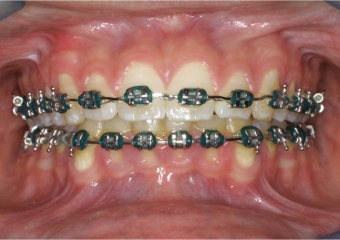

Mordida inicial